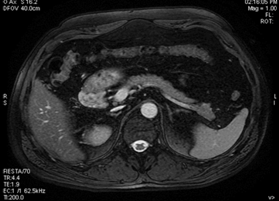

Фотографии медицинских исследований инсулиномы и синдрома Триады Уиппла